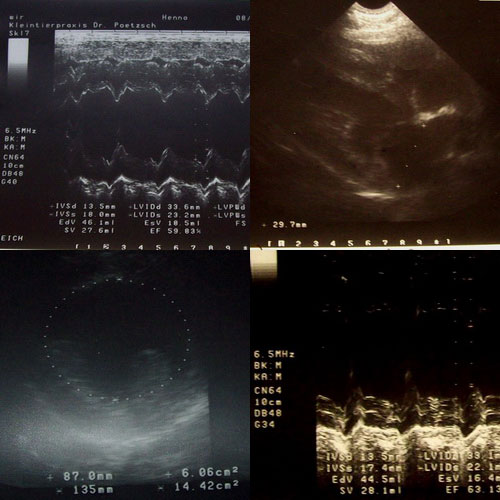

Ultraschalluntersuchungen

EKG